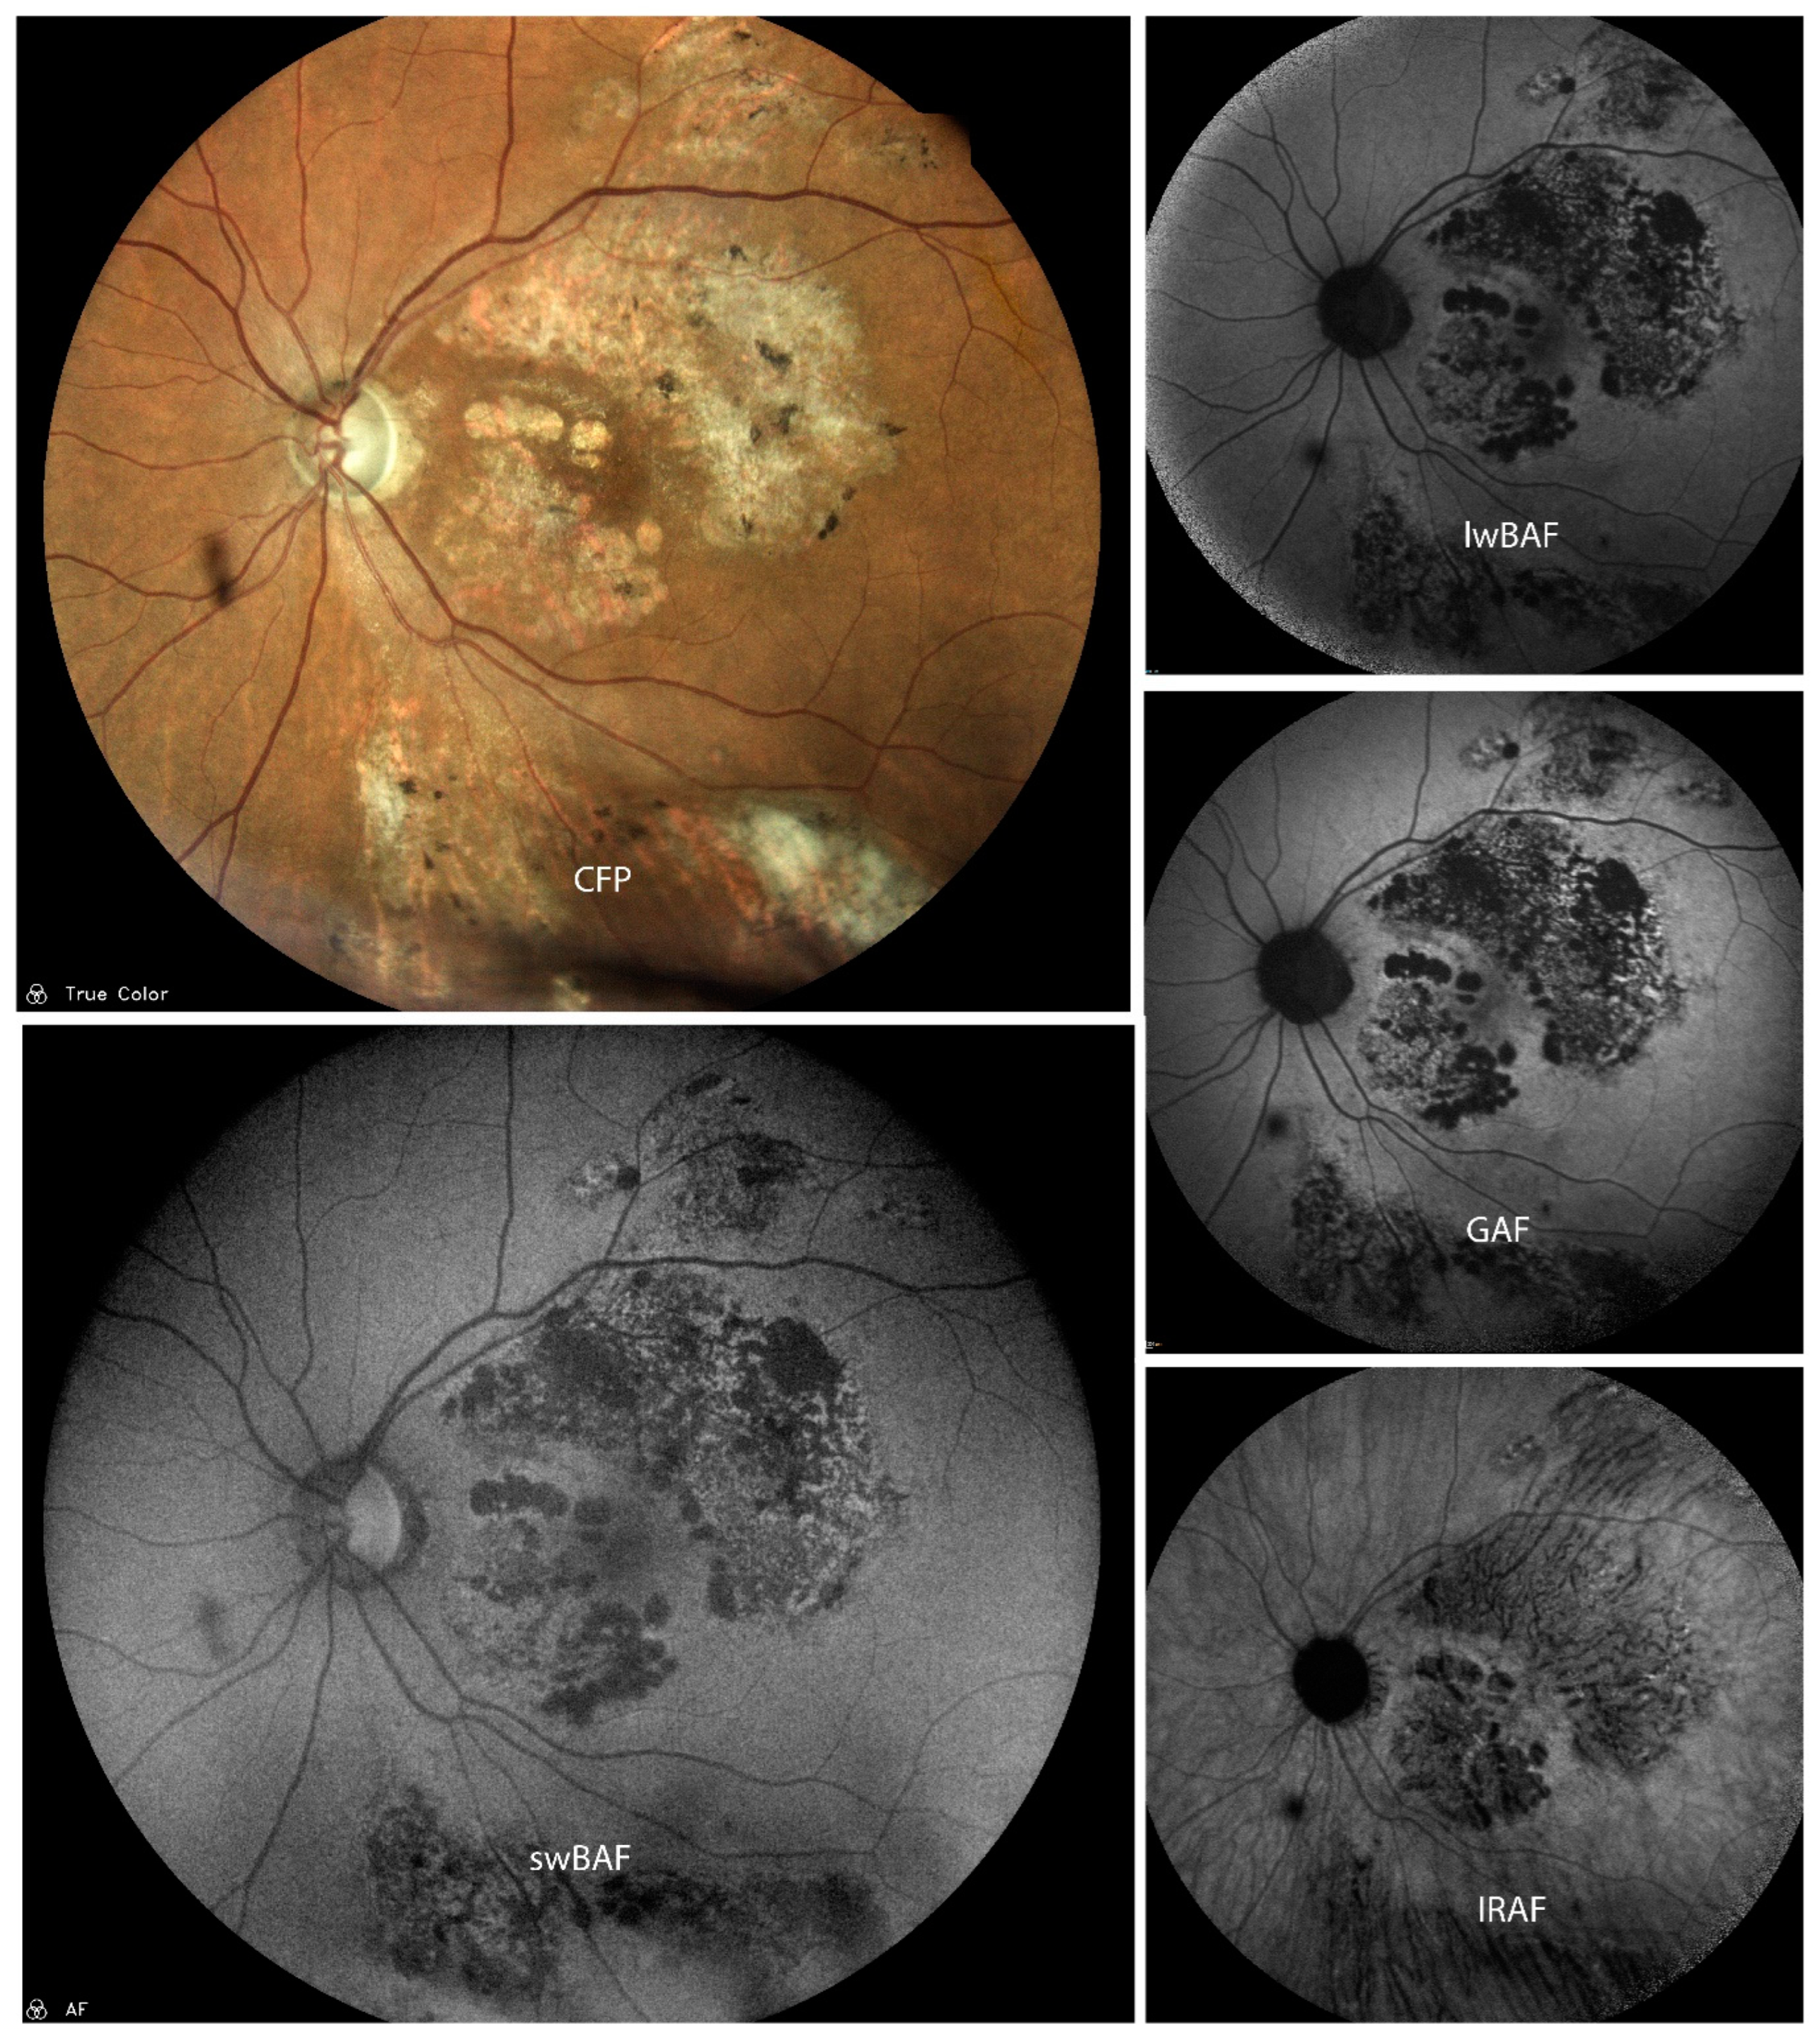

3.1.5. Serpiginous Choroiditis (SC)